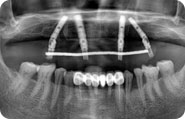

口腔情况:张先生上牙掉的没剩几颗,装的假牙咬合力不好,已经十年不识肉滋味了。

治疗方案:立得用种植牙体系

主诊医师:赵振宇医生